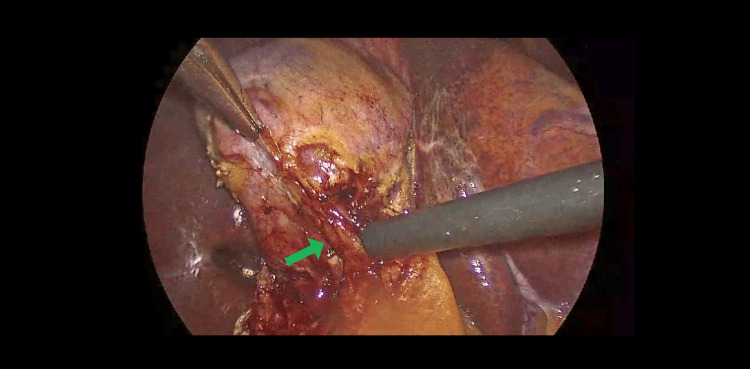

Intraoperatively, dissection of Calot’s triangle proved exceptionally difficult due to unclear anatomical structures. A retrograde (fundus-first) dissection approach was adopted; however, the anatomy remained ambiguous. With meticulous and cautious dissection, the cystic duct and cystic artery were eventually identified and safely ligated using two proximal and one distal Hem-o-lok clip, as seen in Figures 1, 2.

Subsequent exploration revealed that Hartmann’s pouch of the gallbladder was closely abutting the CHD, suggestive of Mirizzi syndrome (Figure 3), further complicating the surgery. During the procedure, an additional duct-like lumen draining bile was discovered in continuity with the gallbladder, raising suspicion for an anatomical variant (Figure 4). Due to this unexpected finding, an intraoperative cholangiogram (IOC) was performed, which confirmed the patency and integrity of the common bile duct (CBD), CHD, and both right and left hepatic ducts, as demonstrated in Figure 5.